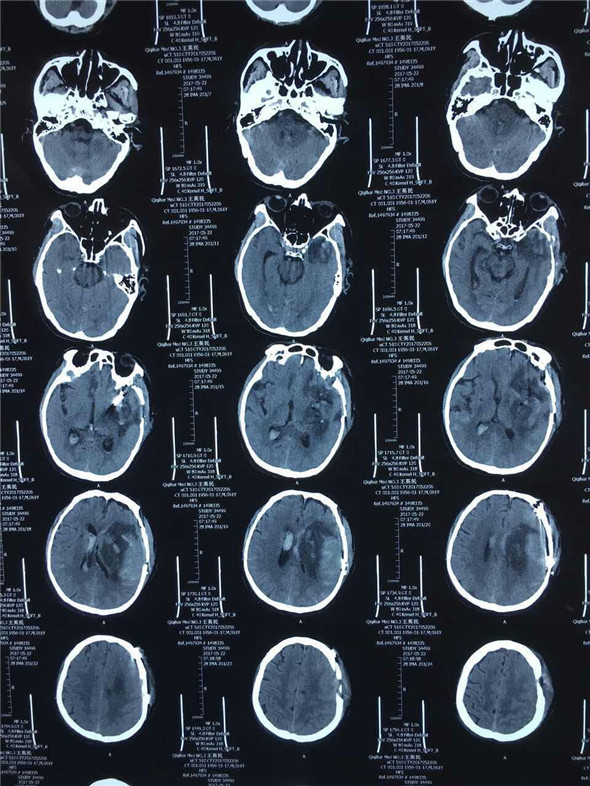

因术前缺少脑256CT及全脑血管选择性造影,动脉瘤的位置、大小情况无从知晓,所以手术切口的设计,术中可能发生的情况的预判,对手术能否成功有着至关重要影响。术中吴主任凭借多年的手术经验及娴熟的手术技巧,仔细而充分的清除颅内血肿,在左侧大脑中动脉M1、M2交界处暴露出动脉瘤,最大直径约1.8cm,2枚动脉瘤夹成功夹闭。经过3个小时紧张而有序的手术,王先生的手术顺利完成。术中将骨瓣成功复位,避免了二次手术,减轻了患者的经济负担,术毕患者双侧瞳孔回复正常,术后第一日患者清醒。

术后头部CT